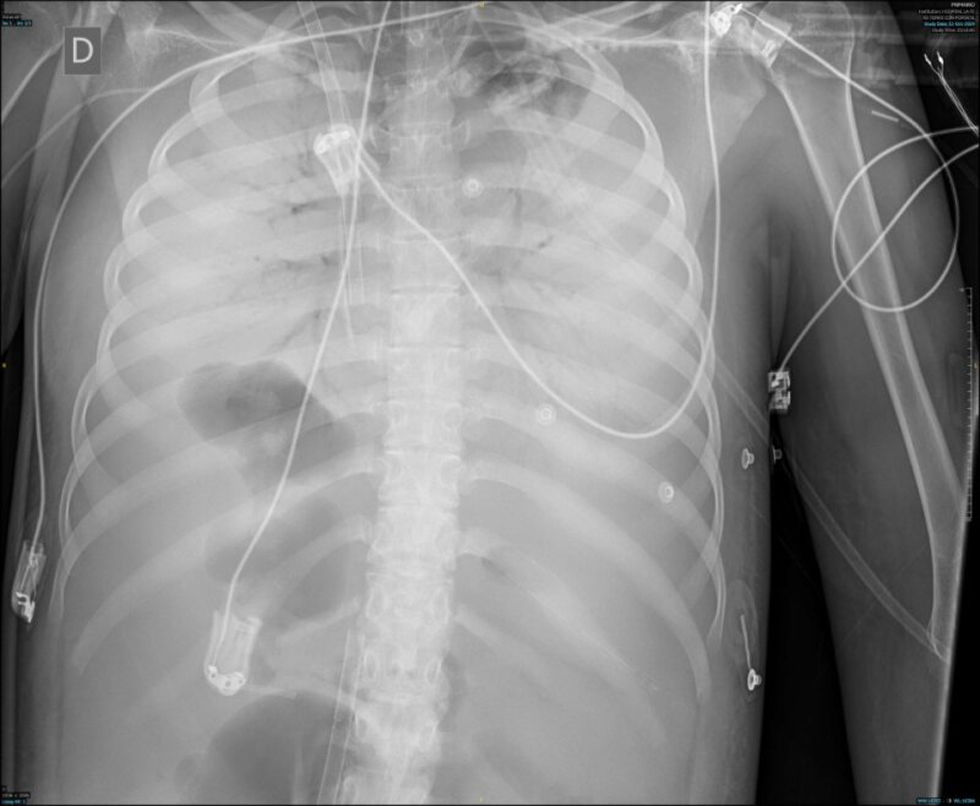

Mujer de 19 años, con antecedente de miopatía de Steinert, intubada por distrés respiratorio grave tras laparotomía exploradora por seudooclusión intestinal. En aspirado traqueal, E.coli sin mecanismos de resistencia. Muy mala mecánica pulmonar (compliance inferior a 2ml/cmH2O) y sin respuesta a maniobra de prono, se canula ECMO veno-venoso y, ante las altas presiones en la vía aérea con 4ml/kg de peso ideal, se cambia ventilación por ventilación con liberación de presión en la vía aérea (APRV): presión alta 15cmH2O; tiempo alto 6s; tiempo bajo 0,3s. Inicialmente 10ml de volumen espirado. La evolución radiográfica se muestra en las imágenes (fig. 1: día0; fig. 2: día2; fig. 3: día5). Este caso es un ejemplo de cómo la ventilación por APRV mientras aseguramos el intercambio gaseoso con el ECMO puede ser útil en el manejo de pacientes con distrés respiratorio refractario.